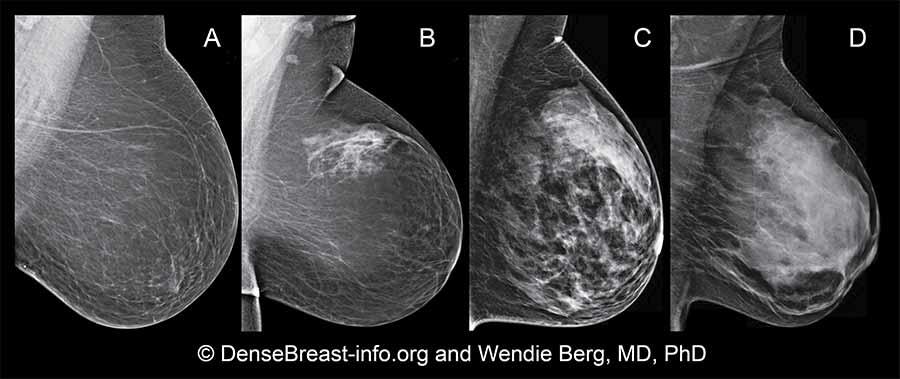

Los médicos usan un sistema de informes y registro de datos de imágenes mamarias llamado BI-RADS para clasificar la densidad de la mama. Este sistema creado por el Colegio Estadounidense de Radiología (ACR) ayuda a los médicos a interpretar y preparar el informe con los resultados de la mamografía. Los radiólogos son médicos que interpretan las radiografías. En el BI-RADS se usan cuatro categorías para clasificar la densidad de la mama:

• Tejido de mama predominantemente graso (adiposo): casi todo el tejido de la mama es graso. Se encuentra en alrededor del 10 % de las mujeres.

• Tejido de mama fibroglandular disperso: casi todo el tejido de la mama es graso, con algunas áreas densas de tejido glandular y tejido conjuntivo fibroso. Se encuentra en alrededor del 40 % de las mujeres.

• Tejido de mama heterogéneamente denso: el tejido de la mama tiene muchas áreas densas de tejido glandular y de tejido conjuntivo fibroso, con algunas áreas de tejido graso. Se encuentra en alrededor del 40 % de las mujeres.

• Tejido de mama extremadamente denso: casi todo el tejido de la mama es tejido denso glandular y tejido conjuntivo fibroso. Se encuentra en alrededor del 10 % de las mujeres.

Imágenes de una mamografía mostrando las cuatro categorías para clasificar la densidad de la mama: A) tejido de mama predominantemente graso (adiposo); B) tejido de mama fibroglandular disperso; C) tejido de mama heterogéneamente denso; D) tejido de mama extremadamente denso.

Si recibe un informe de mamografía que indica que tiene mamas densas, significa que en la mamografía se observó que el tejido de mama es heterogéneamente denso (C) o extremadamente denso (D).